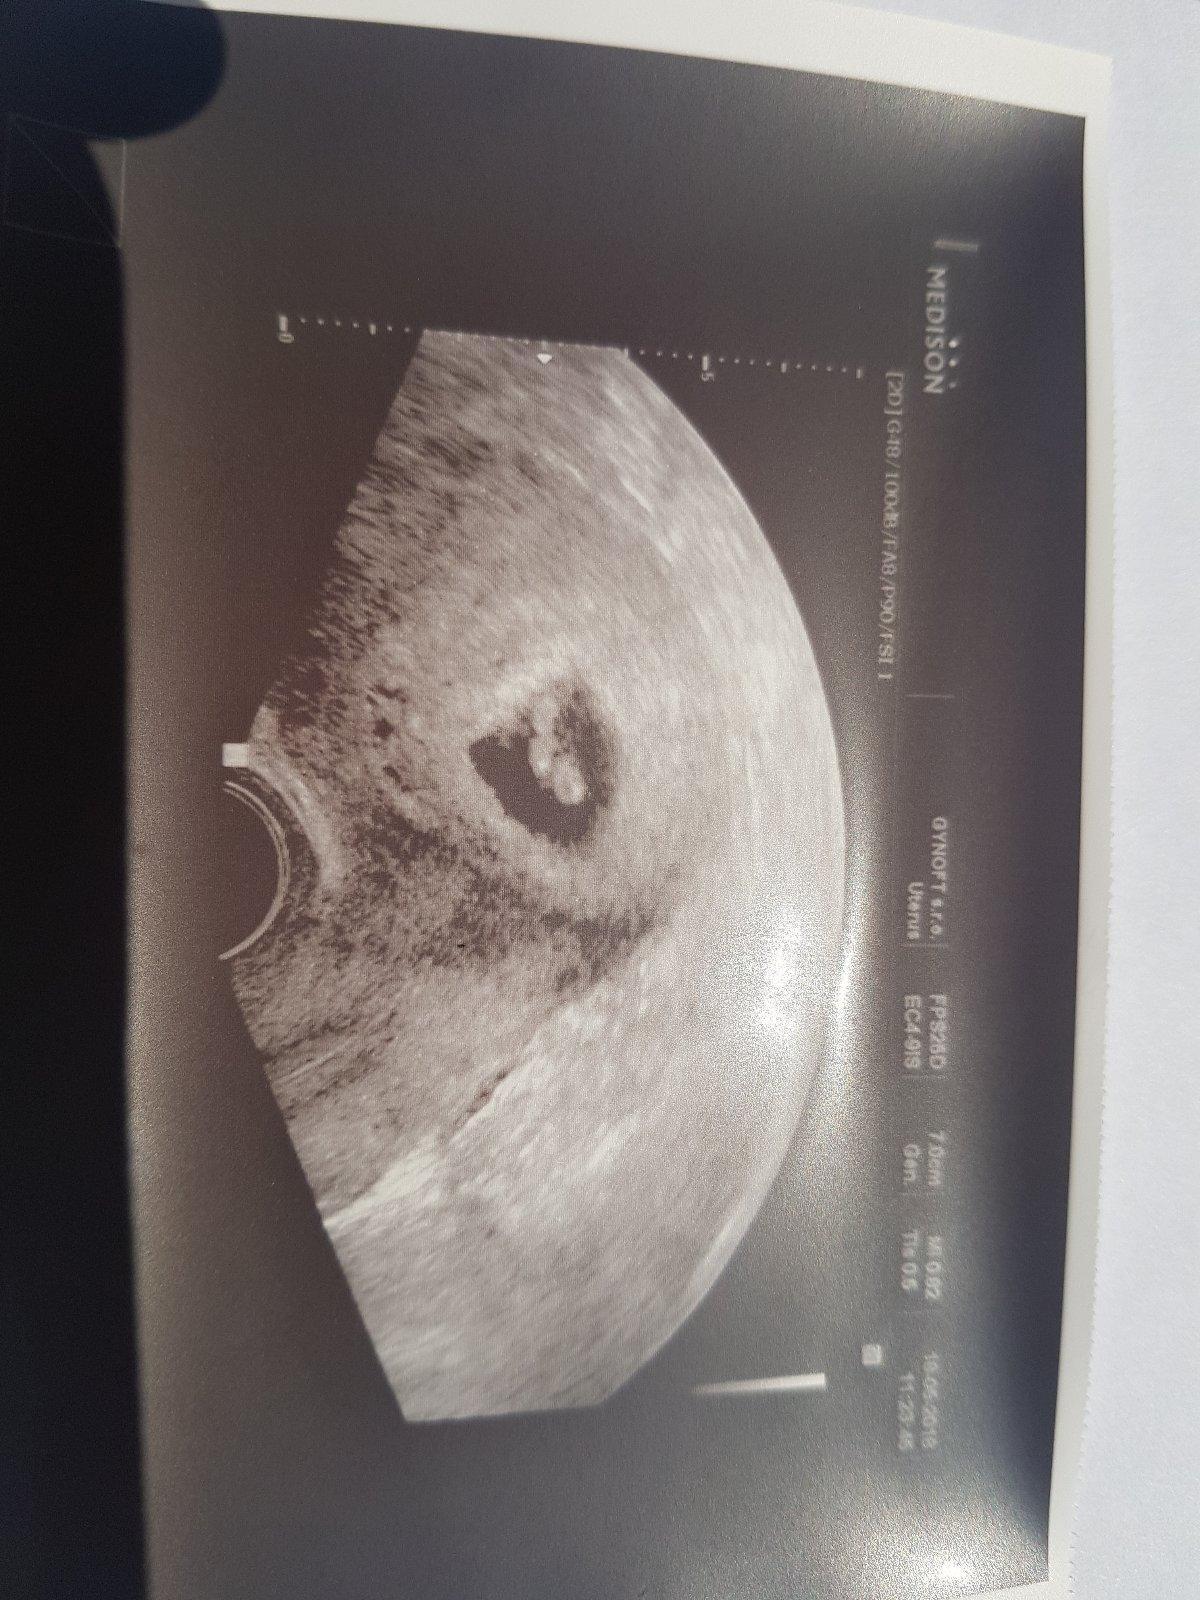

@priefi na fotce nevim.. ja to nepoznam 😓 ale dr. rikala ze srdicko bije

Můj Dr. Podle prvního utz hned prohlásil že jde o zamlkle těhotenství byla sem 5tt a hned mě poslal na přerušení ale nesla sem a našla jineho Dr. A dnes na UTZ srdíčko a odpovídající velikost tak sem ráda že sem neposlechla a nesla na přerušení